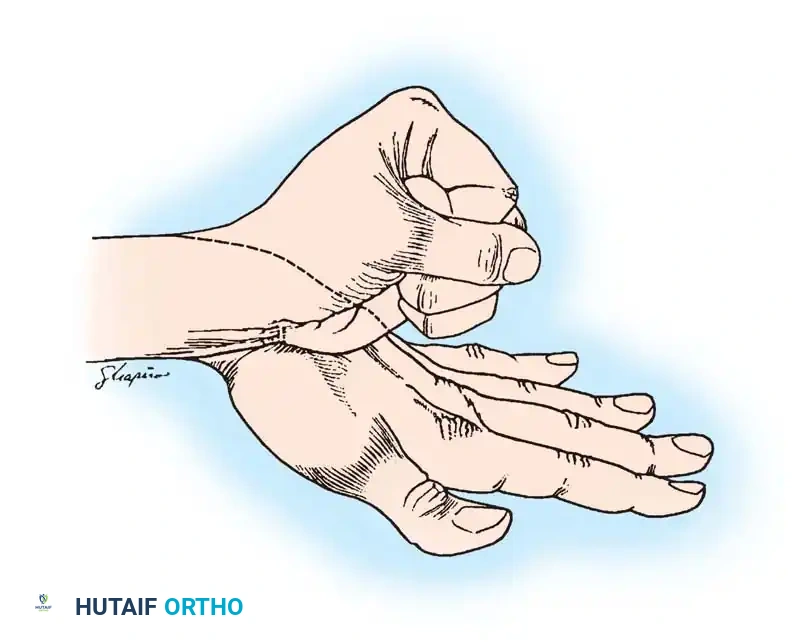

Preoperative clinical presentation of a severe radial clubhand deformity, demonstrating the characteristic radial deviation, volar subluxation, and prominent ulnar styloid region.